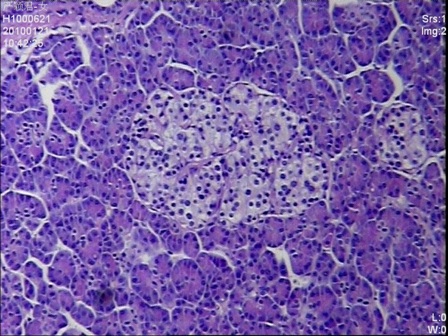

Figure 3: Multiple enlarged islets were diffusely present in the pancreatic parenchyma with variations of the size and number of cells in the islets (H&E stain, 200 x magnifications)

Given the negative preoperative findings, exploratory laparotomy was performed 16 days after admission. No pancreatic mass was detected by palpation or by intraoperative ultrasound. Selective intra-arterial calcium stimulation with selective venous sampling of the splenic, superior mesenteric and portal veins (Figure 1) showed an elevated insulin level of 1230.7mIU/L within the distal splenic vein. (Table 1) Distal spleno- pancreatectomy was performed. (Figure 2) Histopathology showed nesidioblastosis with ductuloinsular complexes and insulin-positive cells budding off the duct epithelium. Focally, the distribution of islets was densely crowded. In the majority of islets, multiple β-cells with enlarged and hyper chromatic nuclei and abundant clear cytoplasm were identified (Figure 3 and 4). Immuno histochemically, the number of insulin-secreting β-cells was increased, and the number of glucagon secreting α-cells was decreased.